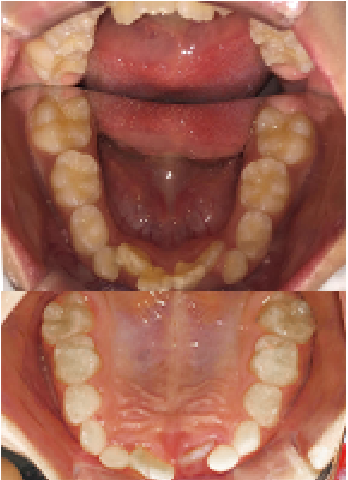

症例 : 7歳 女性

Before

After

主訴

叢生(歯がガタガタ)

治療方法

床矯正+インビザラインファースト

総額治療費

550,000円(税込)

治療期間

3年

治療のリスク・副作用

前歯を正しい位置に移動する時に、咬み合わせが不安定になることがあります。

改善ポイント

左側の前歯が反対咬合のため、床矯正だけでは改善が難しく、インビザラインファーストを併用しました。

少しずつ動かしていく必要があるため、治療期間もやや長くかかりましたが、綺麗な歯並びになりました。